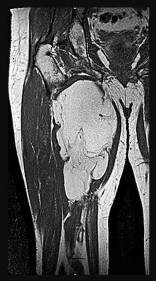

Figures 7a through 7d are the radiograph, MR images, and biopsy specimen of a 35-year-old man who has a painful, slowly enlarging knee mass. Which chromosomal translocation is characteristic of this pathology?

Synovial sarcoma is a soft-tissue sarcoma that usually occurs in young adults. Synovial sarcoma often causes pain, unlike most soft-tissue sarcomas, which generally do not cause pain. Imaging characteristics include soft-tissue calcifications on plain radiographs and a heterogeneous mass that is generally isointense to muscle on T1-weighted images and hyperintense to muscle on T2-weighted images. There are biphasic and monophasic types of synovial sarcoma. The biphasic

type, which is depicted here, has both spindle cell and epithelial components and will stain for both vimentin and cytokeratin. More than 90% of patients with synovial sarcoma have a characteristic genetic translocation of t(X;18), which results in the fusion protein SS18-SSX. This translocation can be stained for use of florescence in situ hybridization technology. t(11;12) is seen in Ewing sarcoma. T(9;22) is seen in extraskeletal myxoid chondrosarcoma. t(12;16) is seen in myxoid liposarcoma.